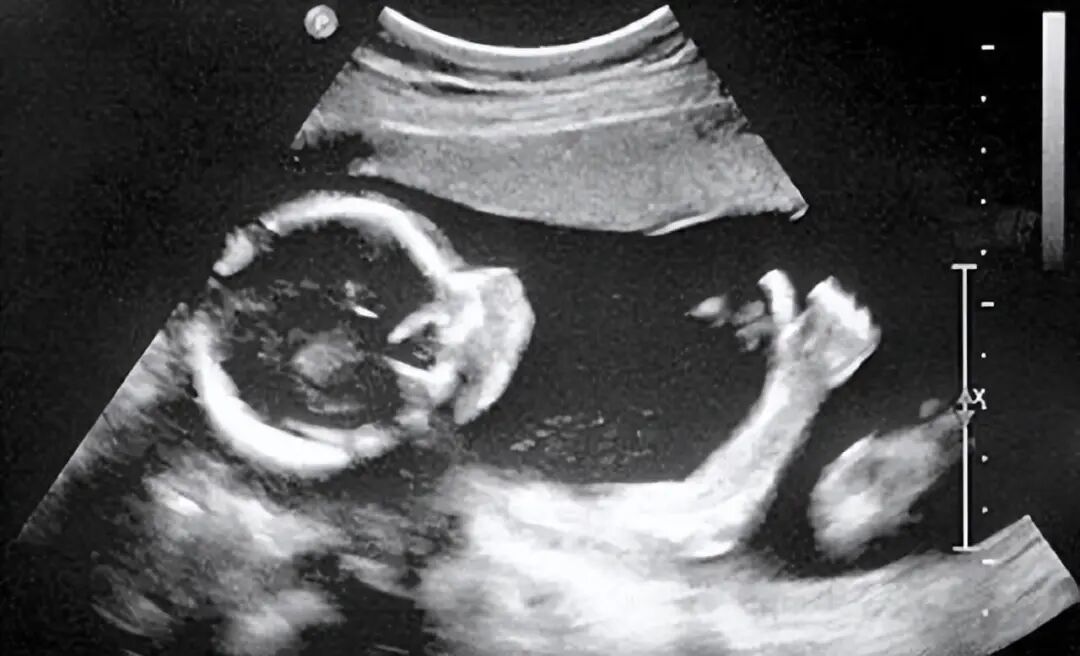

这天,王世芬请了假,在工友的陪同下做了全身体检。本以为只是简单的消化不了,但医生拿着B超单仔细端详后说:“你怀孕了!”

原来王世芬的腹部长了肿瘤,隐约看起来像怀孕三个月的胎儿。她担心再次误诊,又找到妇产科医生询问情况,得到了相同的回答。

“肿瘤!已经长成如胎儿一般大了!如果不尽快切除,会影响未来生育。”